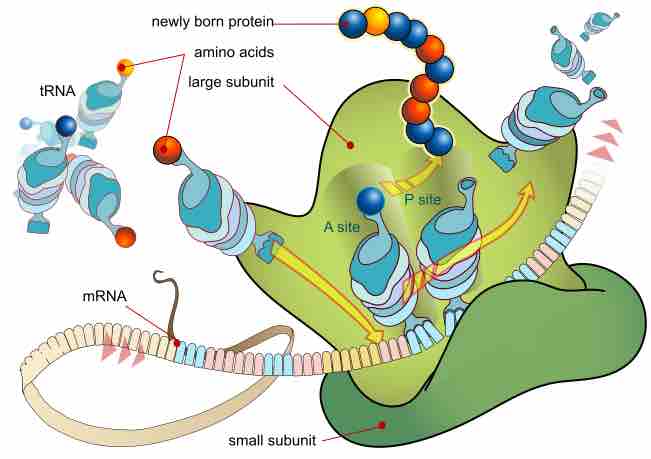

Protein synthesis inhibitors are substances that disrupt the processes that lead directly to the generation of new proteins in cells.